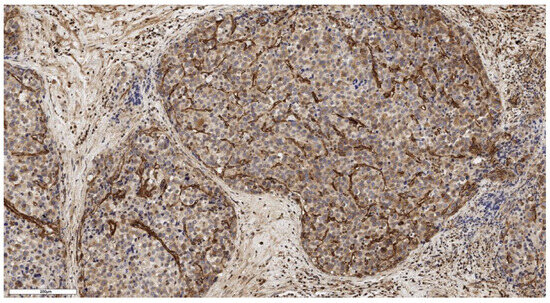

Figure 2.

Conventional subtype of ACC. The parenchyma of the tumor. IHC reaction with CD90 marker, ×100. Scale bar = 70 μm.